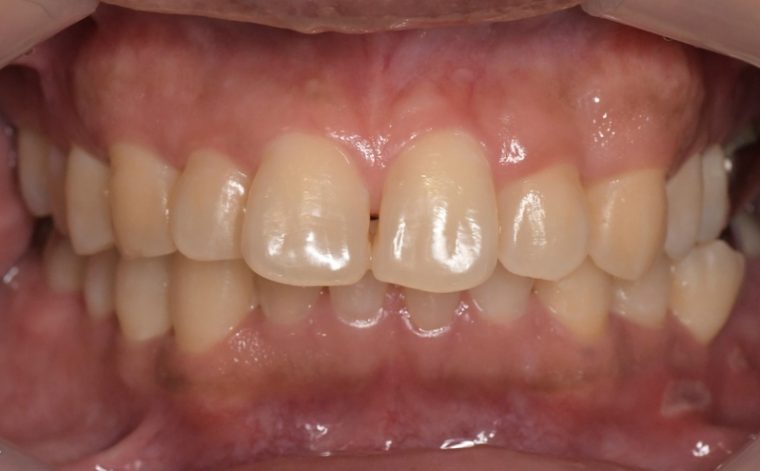

健康な歯ぐきの特徴

健康な歯ぐきは、綺麗なサーモンピンク色で、歯と歯の間が三角形でうまっています。近くで見ると、表面にみかんの皮のような細かなつぶつぶがあります。痛くない程度の力で歯ブラシの毛先を歯ぐきに当てて磨いてみましょう。出血が起こらなければ、健康な状態だといえます。

健康な状態の歯ぐきの写真

軽度歯周病の歯ぐきの写真

中等度歯周病の歯ぐきの写真

重度歯周病の歯ぐきの写真